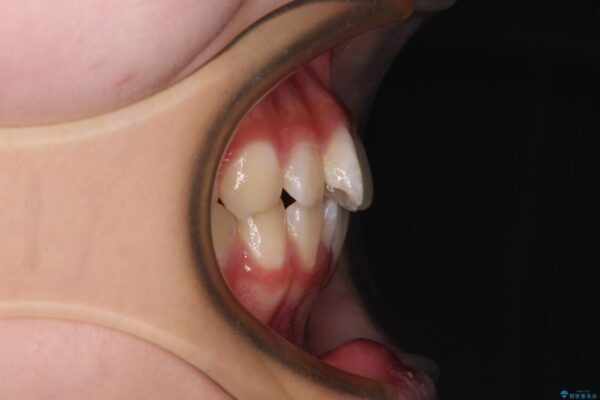

上下前歯のねじれを気にして来院された患者様です。

ワイヤー矯正でもマウスピース矯正でも対応可能でしたが、マウスピース矯正の自己管理が面倒であること、上顎前歯の捻転が著しいことから、ワイヤー矯正での治療を希望されました。

治療前

• インビザラインは使える自信がない ワイヤー装置にて矯正治療 治療前画像